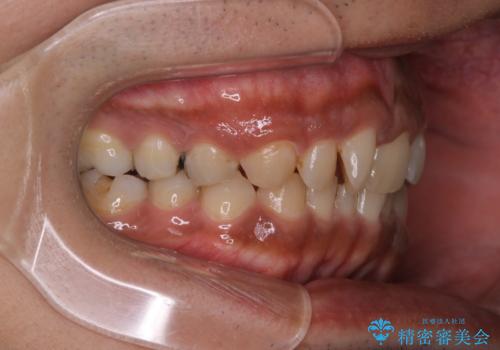

【モニター】インビザライン 前歯の捻れを治したい

- 30代男性

- 矯正装置

- インビザライン

- 治療期間

- 1年6ヶ月

- 上下の前歯のがたつきを主訴に来院されました。インビザラインで治療可能と判断致しましたので、IPR(歯と歯の間を削る処置)と歯列弓拡大をして

がたつきをとる治療計画を立てました。

マウスピースをしっかり使用していただいたことで、主訴である前歯のがたつきも改善され

リファイメントも1回のみで治療を終了することが出来ました。